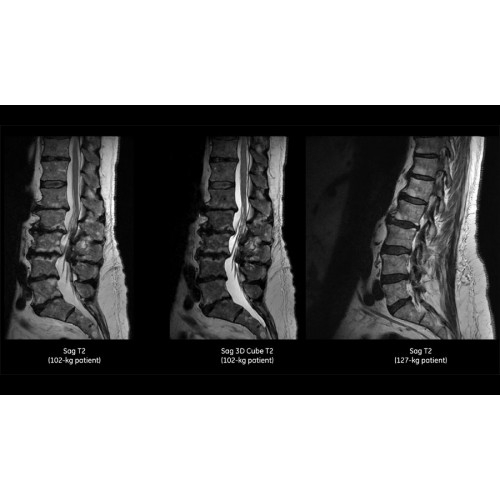

МРТ аппарат GE SIGNA Voyager 1.5T позволяет проводить полный спектр магнитно-резонансных исследований, включая нейровизуализацию, исследования опорно-двигательного аппарата, органов брюшной полости и малого таза, а также специализированные кардиологические программы.

• Ортопедия и травматология